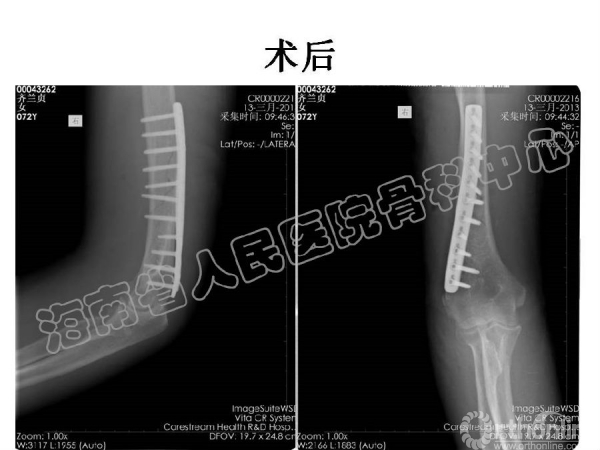

2014-04-14 文章来源:海南省人民医院骨科中心 沈宁江 我要说